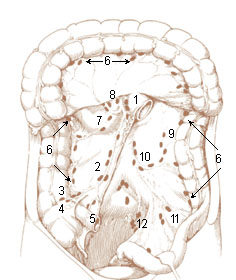

Figure 15 From Learning The Nodal Stations In The Abdomen. | Semantic

www.semanticscholar.org

www.semanticscholar.org

stations abdomen nodal